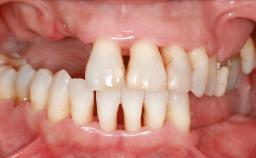

A 47-year-old Caucasian woman with a single-tooth edentulous space at the site of the left maxillary canine was referred for treatment. She had undergone traumatic extraction of this impacted canine several months before referral. Her chief complaint was the dissatisfying appearance of her smile. The patient desired a stable and esthetic rehabilitation of the site. Her dental history showed no evidence of periodontal disease or bruxism. She had no systemic diseases, was not taking any medications, and did not smoke. The extraoral examination revealed a high lip line and an inadequate soft-tissue volume at the defective canine site. Large black triangles were visible between the canine and its adjacent teeth.

Lip Line No exposure of papillae Exposure of papillae Full exposure of mucosa margin

Soft Tissue Anatomy Intact Defective

Bone Volume Horizontally and vertically sufficient Horizontally deficient Deficient vertically or deficient vertically AND horizontally